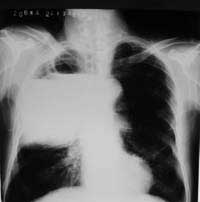

以下是引用woaixct在2006-6-23 12:15:00的发言:[br]第一张胸片示:右肺上叶为大片致密影占据,左肺上见大片致影及空洞性病灶并有液平;[br]第二张胸片示:左肺上叶致密影及空洞性病灶基本吸收,而右肺上叶之病灶有少许吸收改变;[br]ct片示:右上叶大片软组织密度,右肺门区至右肺上叶见巨大软组织块,内见支气管充气征,上纵隔右移,主气管及上叶支气受压变扁,中间支气管狭窄,左肺上叶空洞性病灶并有液平,左肺上叶尖后段见大片致密影,结合2张胸片考虑,ct片是4月份所摄,而不是6月份的片子;[br]结合2张胸片及ct片考虑:[br] 1.右中央型肺癌伴右肺上叶不张;[br] 2.左肺上叶尖后段炎性变及左肺脓肿;[br]第2张胸片提示:经过一个多月的不规则抗炎治疗,左肺上叶病灶及右肺上叶不张病灶基本吸收,而右肺占位无明显变化。

以下是引用jiangjing在2006-6-23 21:21:00的发言:[br]个人考虑还是两肺感染性病变可能大,主支气管及叶支气管是通畅的,并可见支气管气相;ct提示病变是以肺叶分布的,密度相对均匀;胸片可见有叶间裂下坠征,是不是考虑克雷伯杆菌感染可能.病人前后两张片比较病变是增多[应该考虑混合感染可能性大,右肺癌待排建议查痰及穿刺检查]